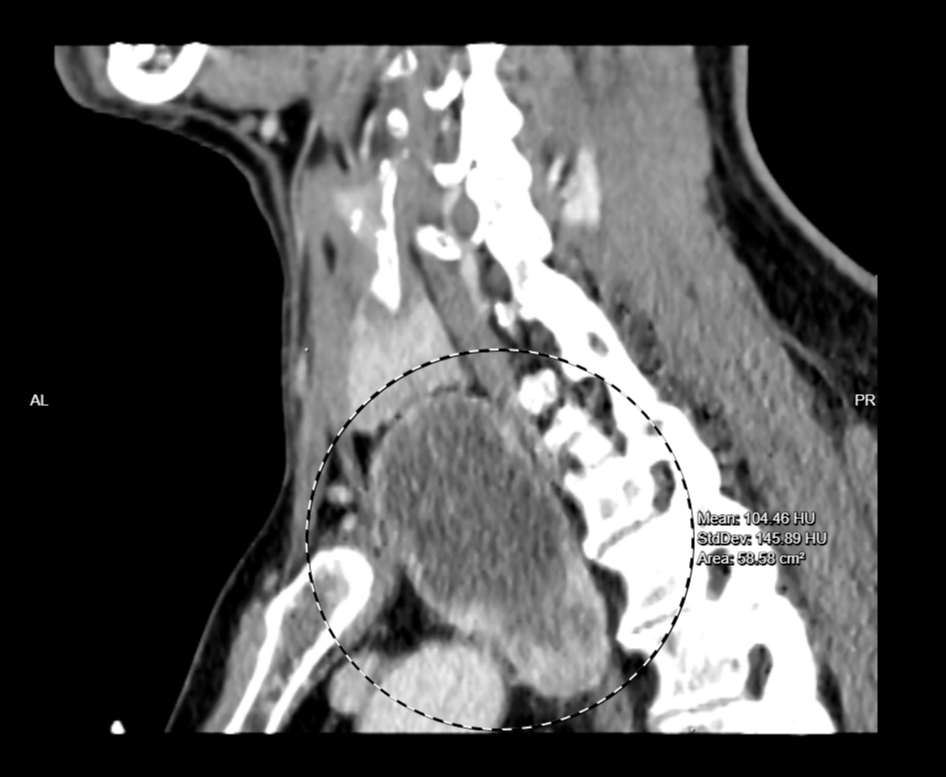

检查见肿物较大,位于主动脉弓后方水平,已压迫气管、食管使其移位,最大直径约5.0cm,未排除神经鞘瘤可能。